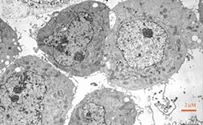

מחקר חדש באוניברסיטת חיפה גילה את תהליך קבלת ההחלטות של תאים המשתתפים בתהליך החלמה מדלקות בגוף: בליעה של 7 תאים שמתו.